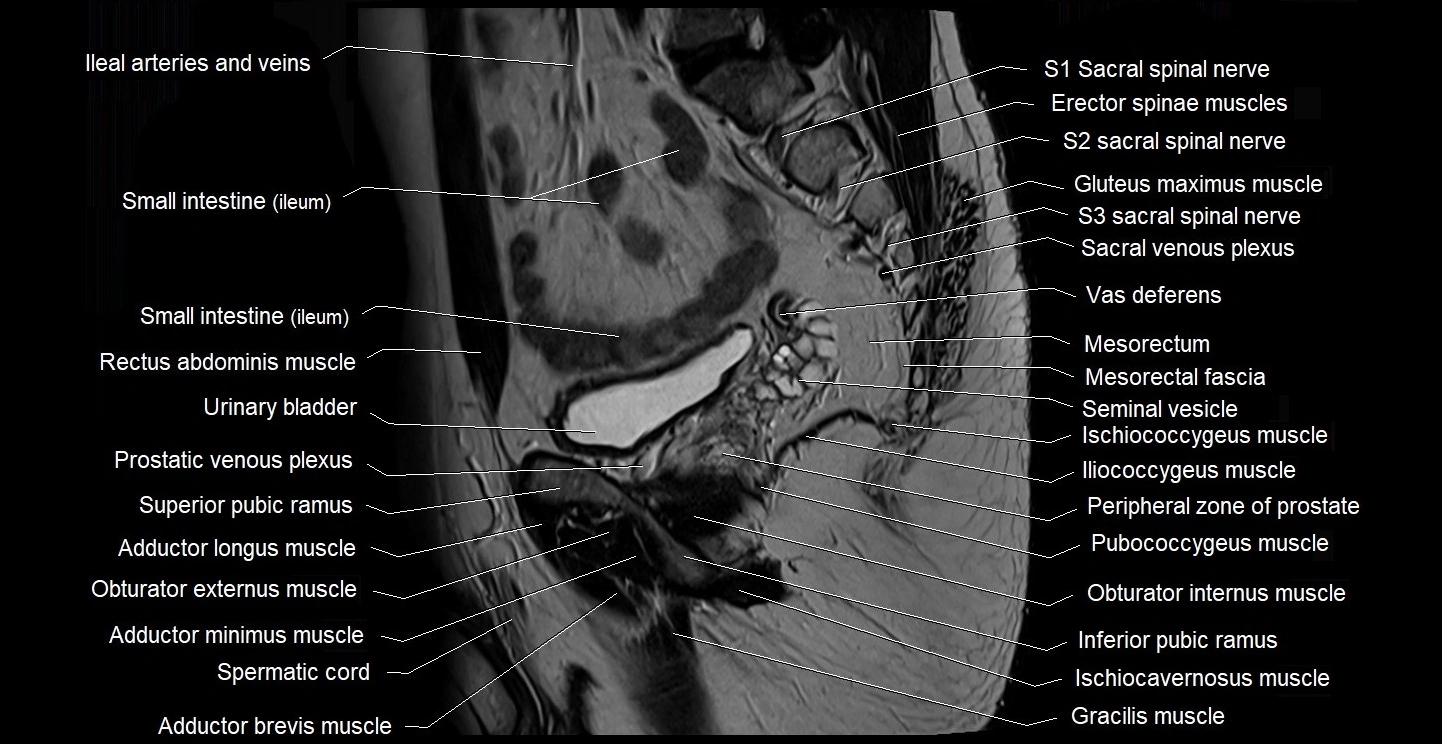

- Anal canal

- Erector spinae muscles

- Gracilis muscle

- Iliococcygeus muscle

- Ischiococcygeus muscle

- Mesorectal fascia

- Mesorectum

- Peripheral zone of prostate

- Pubococcygeus muscle

- Seminal vesicle

- Spermatic cord

- Vas deferens